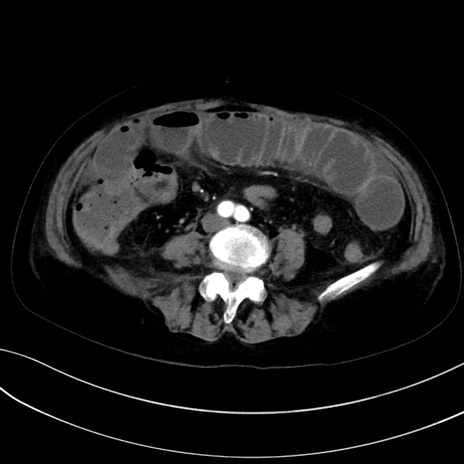

症例13 CT(横断像)1日半後